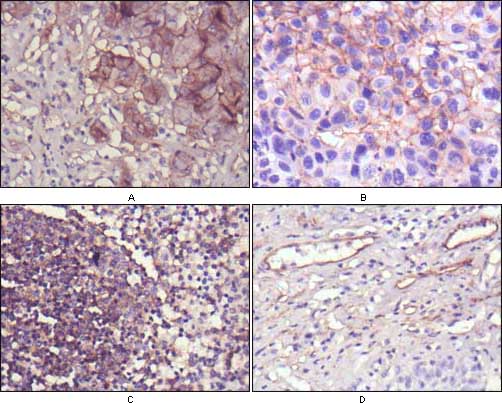

分类: 科研抗体货号: 20375别名: HNF3B; TCF3B; MGC19807应用: WB,IHC反应种属: Human

分类: 科研抗体货号: 20356别名: PAK65; PAKgamma应用: WB,IHC,IF反应种属: Human,Monkey